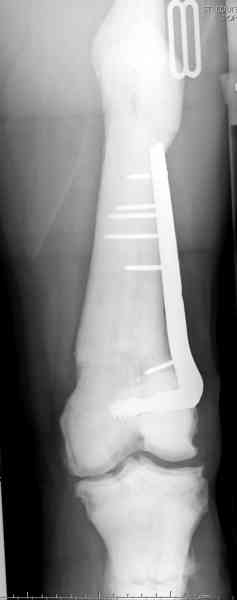

После неудачной попытки скелетного вытяжения в первом мед.учреждении, после осмотра снимков и изучения истории, поставили диагноз “Остеопетроз” или мраморная болезнь, редкая наследственная костная паталогия, где имеется нарушение формации остеокластов.

Конечно, было бы идеальным применение интрамедуллярного остеосинтеза, но учитывая прежний собственный опыт (лечил перелом бедра) и

публикации, предупреждающие о трудностях при обработке кости (иногда из-за неподготовленности инструментария результатом была неадекватная фиксация перелома, или перенос операции из-за фактора усталости оперирующего персонала), решили применить пластину (и в этом же случае был выбран Synthes plate, так что представитель за два дня

зароботал... на десерт тоже).

Заказаны были дополнительные различные дрели, и на следующий день, усиленной бригадой, больного прооперировали, потратив на каждое отверстие около 25-35 минут, хотя сверлили с охлаждением по нарастающей по диаметру сверл и с их заменой каждые 2 мм сверления.

Теперь стоит задача со сращением перелома, из-за отсутствия литературных данных по применению костных стимуляторов при остеопетрозе, и не зная как поведет в этой среде Grafton, все таки надеюсь, что даст толчок к стимуляцию, решил применить пастообразную деминерализованную костную матрицу, расположив спереди между отломками.